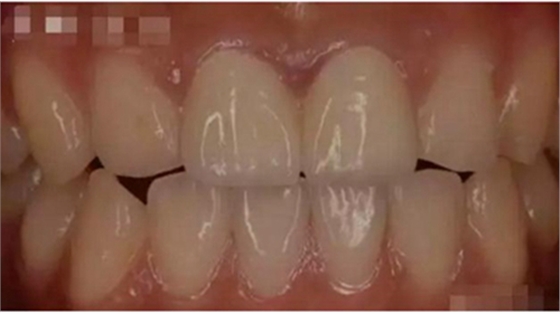

3,美學(xué)效果優(yōu)異

成功的全瓷牙修復(fù)外表逼真美觀、堅(jiān)固耐磨,色澤近似于天然牙,生物相容性良好,不刺激口腔組織,容易清潔,既能回復(fù)牙齒的功能,又有美容的作用。最主要的是全瓷牙具有良好的透明性和折光性,不會(huì)在牙頸部出現(xiàn)黑線,使牙頸部也能達(dá)到良好的美觀效果,這是一般烤瓷牙無法比擬的。

二氧化鋯全瓷牙可用于美容和修復(fù)缺失的牙齒,能對(duì)多顆的牙齒進(jìn)行修復(fù)。是一種強(qiáng)調(diào)整體思維的設(shè)計(jì),因而做出來的牙齒形態(tài)逼真。它的色澤自然逼真,看上去和真牙很相似。并且二氧化鋯全瓷牙具有極好的生物相容性,因而用它來修復(fù)牙齒也不會(huì)出現(xiàn)牙齦發(fā)炎的情況。